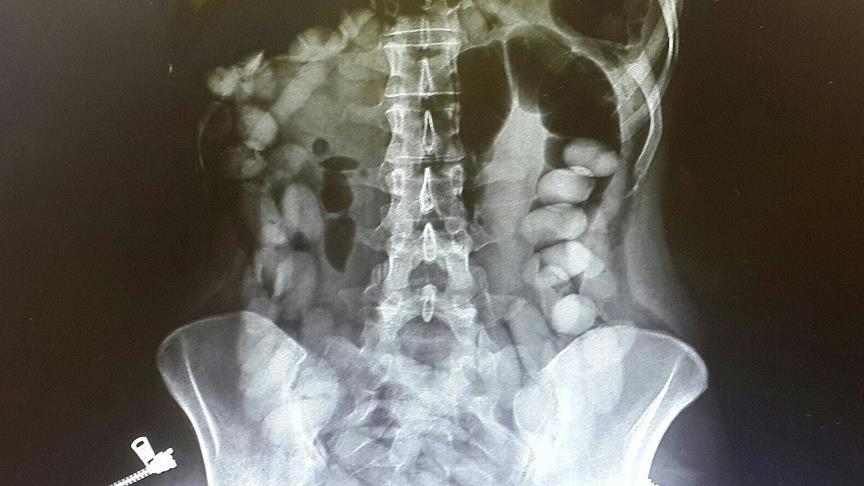

She was stopped by Turkish security forces upon arrival at Antalya Airport and although police did not find drugs in her luggage, a hospital x-ray later revealed dozens of small parcels of cocaine in her stomach.

Each packet contained between 10-12 grams of cocaine.